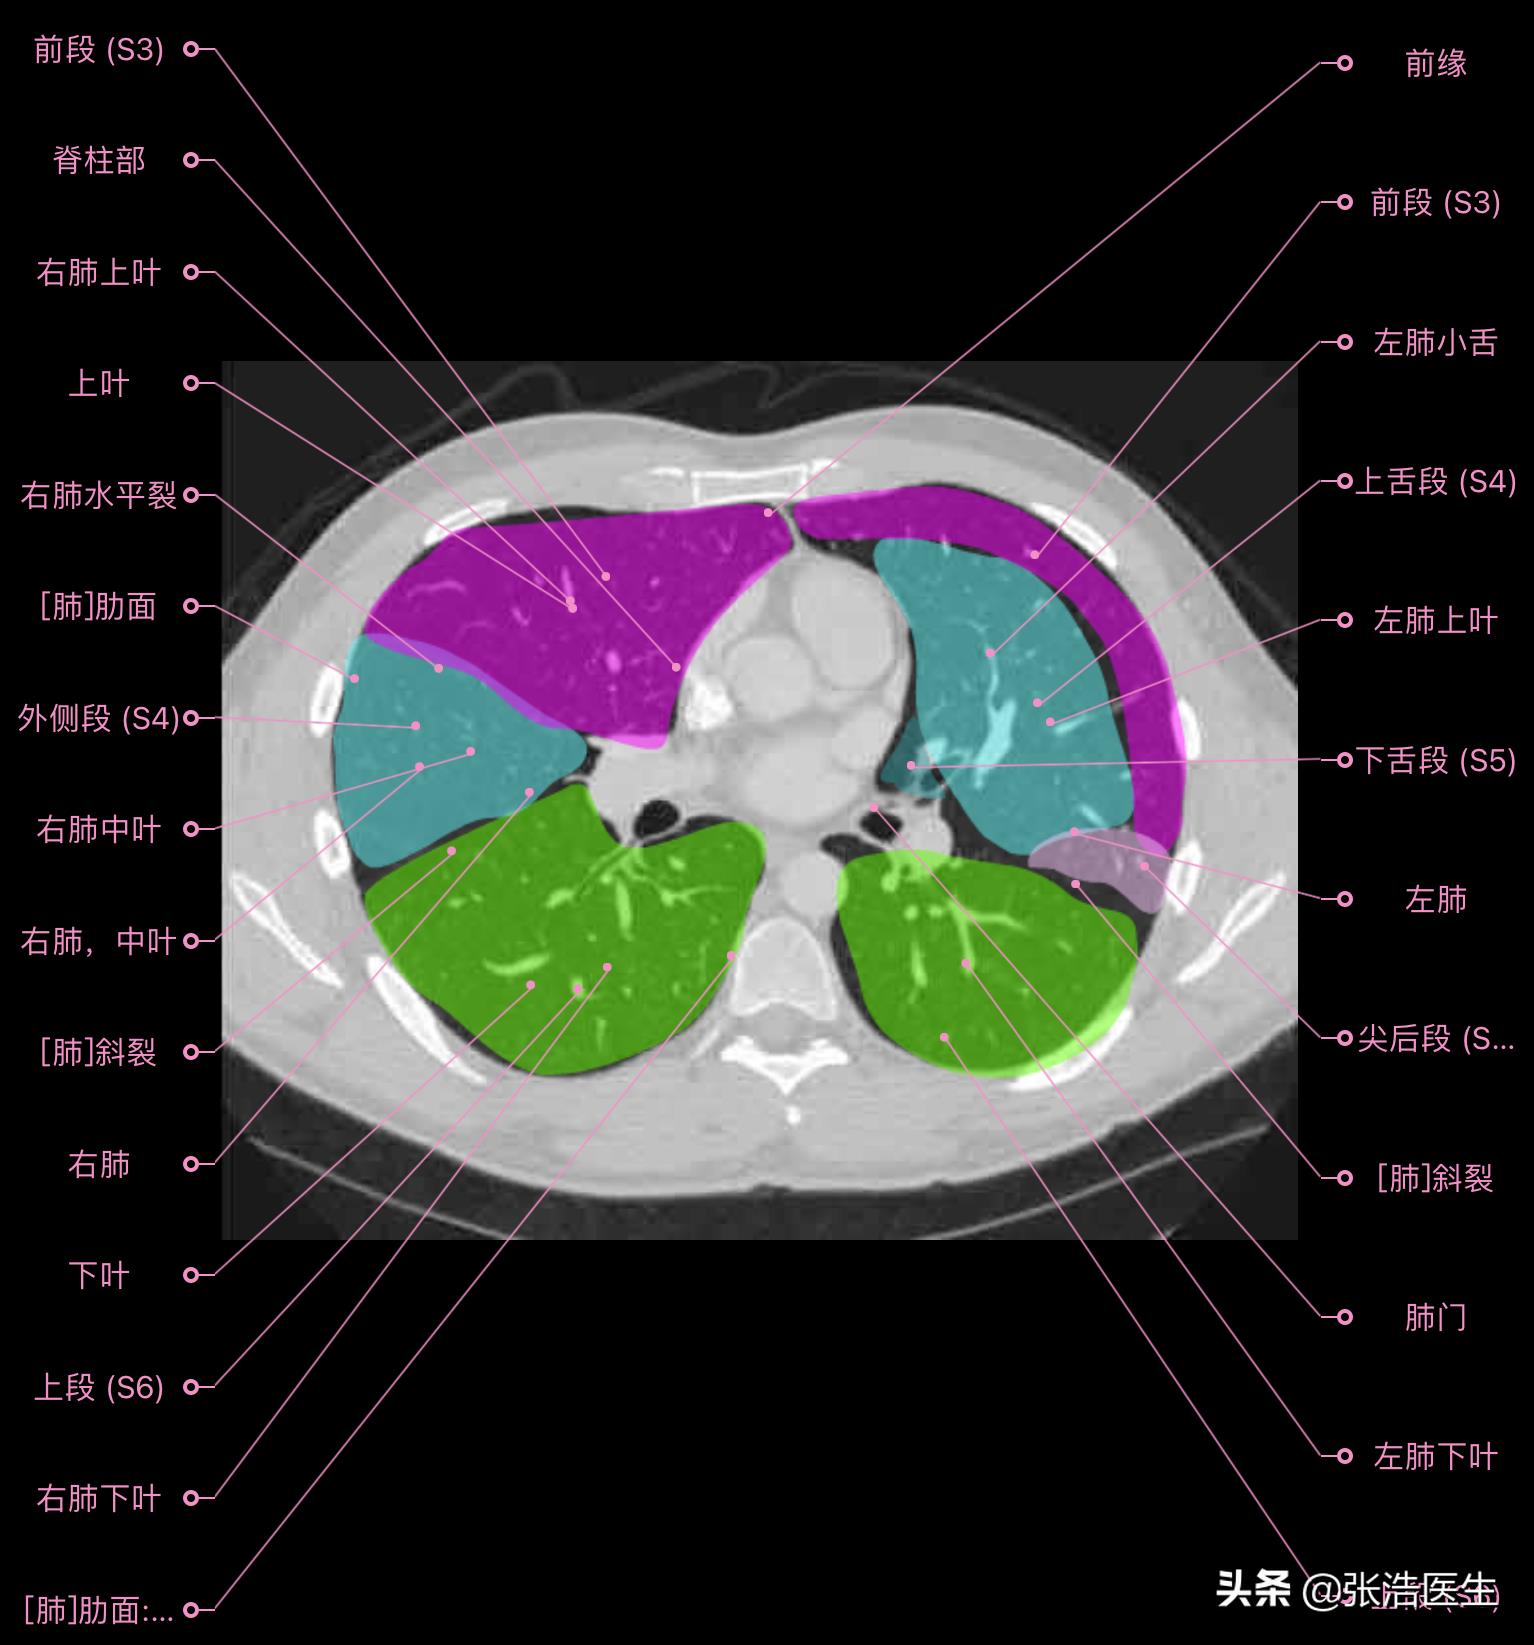

肺部CT横断面高清解剖图谱(图层3)